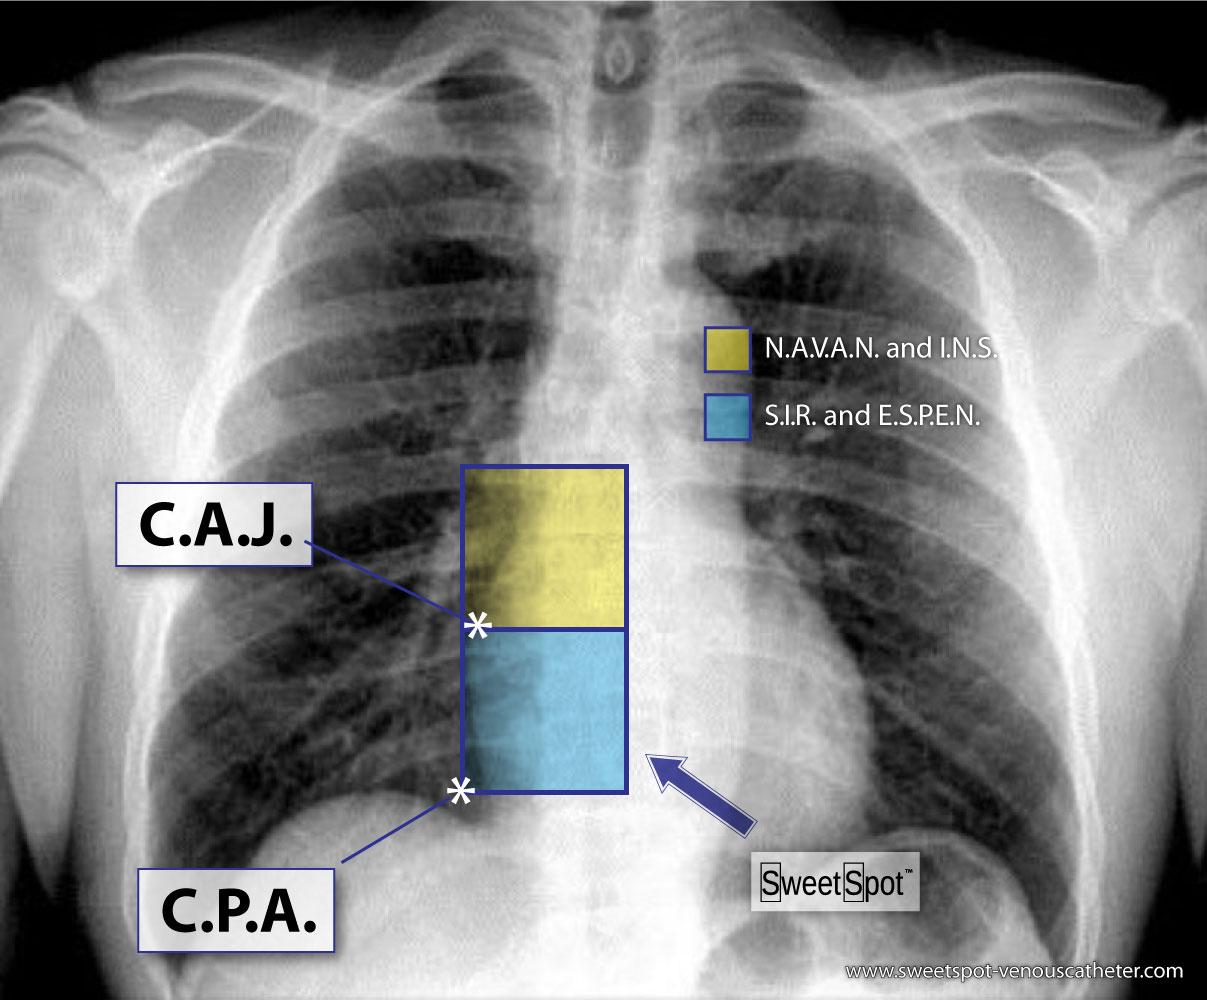

Figure - 19

How to draw the Sweet Spot™ |

Figure - 21

Societal recommendations for V.A.D. catheter tip location |